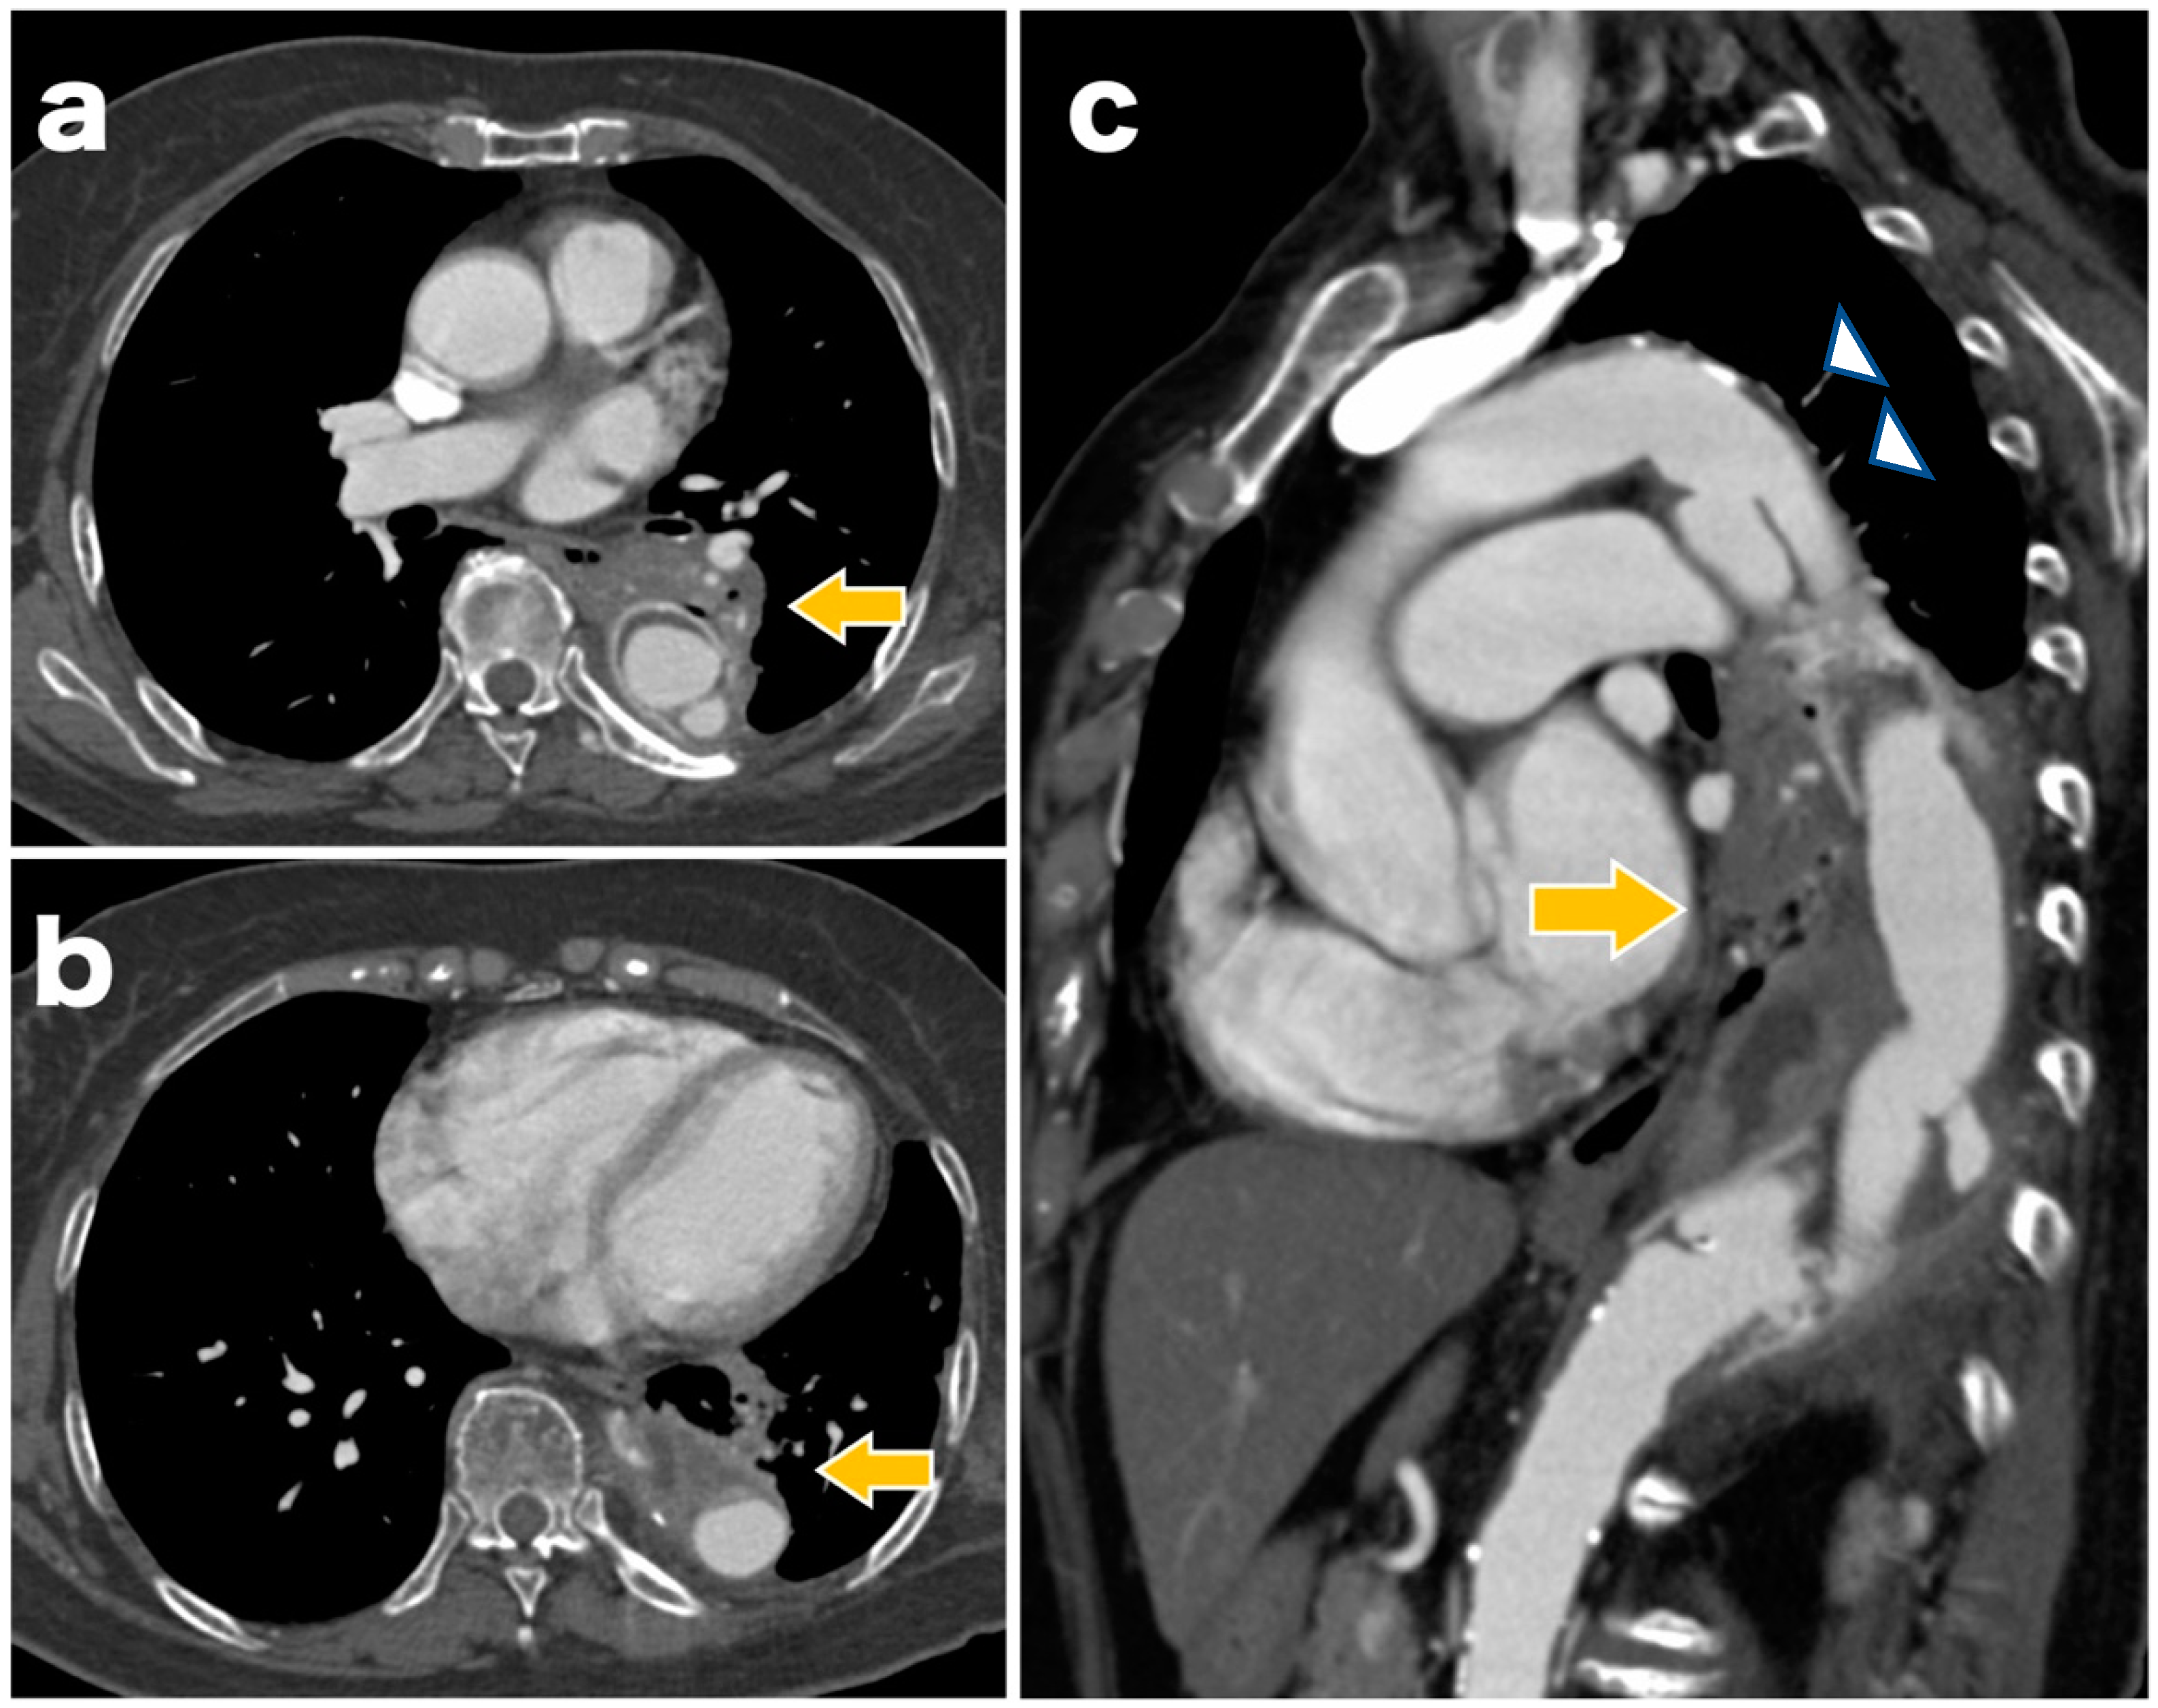

A 77-year-old woman underwent graft replacement of the descending aorta for a descending aortic aneurysm 18 years prior. Postoperatively, aortic dissection was observed at the proximal and distal anastomoses of the graft, and the patient was regularly followed up with computed tomography (CT) in the outpatient department. At 3 months prior to admission, the patient developed a cough with bloody sputum, and due to the persistent symptoms, she was admitted for a thorough examination. On admission, a contrast-enhanced CT scan showed infiltrative shadows and gaseous images in the lung fields around the graft (Figure 1). Gallium scintigraphy also showed abnormal accumulation of gallium consistent with the infiltration shadows and gas images of the lung fields observed on contrast-enhanced CT (Figure 2). Based on these imaging findings, ABF was diagnosed. The patient was considered to be at high risk owing to her advanced age and post-graft replacement of the descending aorta; therefore, TEVAR was performed on the 11th day after admission.

The causes of ABF include thoracic aortic aneurysm, advanced lung cancer, lung infection, and graft replacement or TEVAR for thoracic aortic aneurysms. Among these, previous thoracic aortic surgery is the most common cause, with 55% of all cases including a previous thoracic aortic surgery [3]. It has also been reported that the most frequent site of ABF is between the descending aorta, left lung, and/or bronchus [1,2]. Hemoptysis is a typical symptom, and shock may occur if the amount of bleeding is large [6]. A CT scan may aid in the prompt diagnosis of ABF with infiltrative shadows and hematoma images observed in the lung fields around the aorta. However, fistulas between the aorta and bronchus are rarely directly detectable on CT images [4]. In this case, the patient had hemoptysis, a cough that persisted for 3 months, and underwent descending aorta replacement surgery 18 years ago. In addition, CT images showed infiltrative shadows and gaseous images in the lung fields around the graft, suggesting a fistula between the graft and the left lung and/or bronchus, leading to ABF diagnosis.

Figure 1. Contrast-enhanced computed tomography scan on admission showing infiltrative shadows and gaseous images in the lung fields around the graft (arrow). Although we could not directly signify the fistula between the aorta and the bronchus, the clinical history and CT findings led to the diagnosis of aortobronchial fistula ((a,b): axial images; (c): sagittal image). Chronic aortic dissection findings are also observed on the proximal side of the graft replacement (arrowhead). CT, computed tomography.